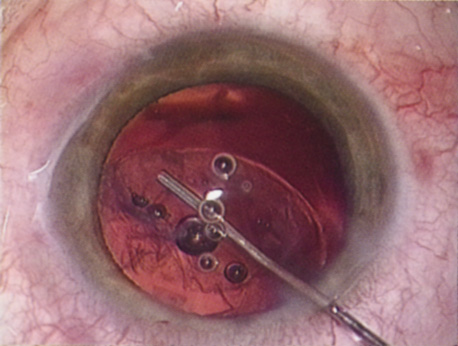

A mature cataract precludes visualization of the fundus. A B-scan ultrasonographic examination provides a real-time, two-dimensional (2D), cross-sectional image of the globe along the marked axis of the probe (Fig. 3). Cataracts are more common in patients with chronic retinal detachment, prior trauma, or intraocular tumors; therefore, a B-scan study is helpful in excluding structural posterior segment pathology before surgery on a mature cataract. Although a negative result to B-scan evaluation is reassuring, the surgeon should remember that it does not predict postoperative visual outcome. The B-scan can be thought of as a picture of Cincinnati from an airplane; the office buildings may all be standing, but you cannot tell whether the people in them are working.